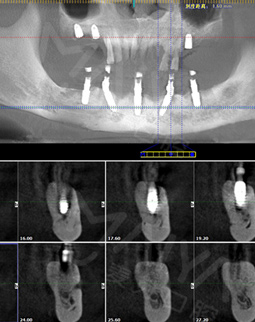

麦芽的博士专家团在看过我的片子后发现,我的牙齿由于长期对口腔疏于护理,牙周情况非常差,余牙有些松动,且牙槽骨萎缩严重,现存的骨量无法进行传统的种植牙手术,因此给我设计了“all-on-4”种牙技术的升级版本“all-on-5”,前期是要处理我的牙周问题,当天就给安排了洁牙,然后上药,等牙周恢复差不多就可以进行种植了!

经过一个月的牙周治疗,牙齿肿胀部分都已经消退,来麦芽种牙之前,心理还有点小紧张,总害怕种牙特别疼,恢复时间慢。我的牙齿情况比较复杂,部分牙齿有牙槽骨吸收,经过前期的各种检查,医生说我的身体状况适合种牙。

但是打完麻药,躺在那里发现手术时一点感觉也没有,半口牙只种了5颗牙钉,而且不到一个小时,感觉自己就眯了一会就好了。麦芽的种植专家们手法特别棒,很稳。牙钉种好之后,没有立即戴牙冠,医生用硅橡胶取模,为我制作了临时牙冠,不过看到临时牙冠我就能想象到完全种好牙的样子了!然后,医生给我一个小卡片,上面记录了种牙后的注意事项,告诉我种完牙后自己维护也很重要。医生说要按时复诊,也会有专门的工作人员进行通知,不得不说麦芽在细节上真的很暖心。